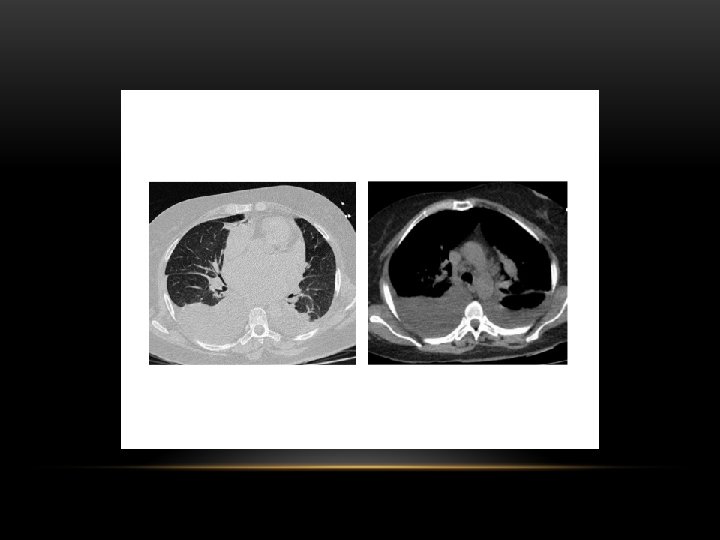

Supine projection erect projection

Pleural Effusion Fluid accumulates in the pleural space. Irrespective of the nature of fluid, radiologically they will look similar. Radiological criteria are: Density In dependent portion (Costophrenic angle in PA view). Blunting of costophrenic angle Lack of identifiable diaphragm (silhouette sign principle).

Causes of pleural effusion: -Infection -Subphrenic abscess. -Malignant neoplasm -Cardiac failure -Pulmonary infarction -Collagen vascular disease -Nephrotic syndrom Modalities for pl. effusion diagnosis: -Plain chest x ray. -Ultrasound -Computed tomography